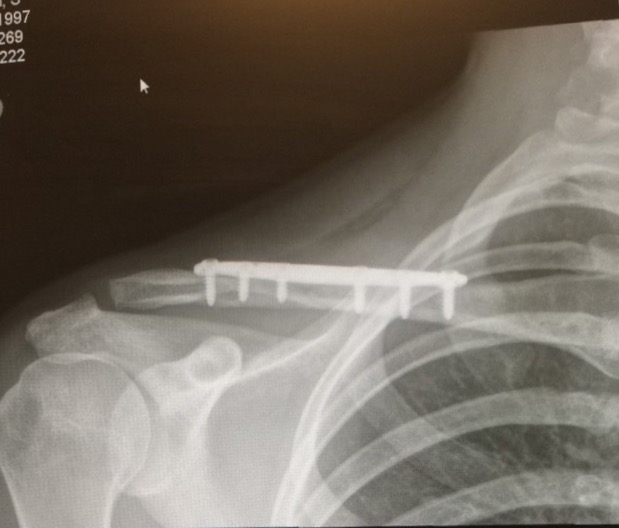

I took an x-ray and couldn't believe the results. My collarbone was in two pieces, on top of each other. You didn't have to be me in order to know how much pain I was in. Dr. Altchek told me that I needed to have surgery the next day. I asked him when I could ride again, and he told me he was going to make sure it was as soon as possible. On Tuesday April 21, 2015, I sat waiting to go into surgery. I was terrified. I thought I wasn't going to wake up. Nearing 6:00 pm, Dr. Altchek was ready for me. It was his 15th surgery of the day. That scared me.